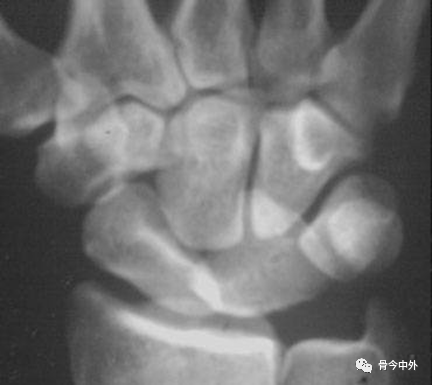

3.腕骨弧线

Gilula 提出三个平滑的弧形勾画出近侧列和远侧列腕骨。弧 I 把舟骨、月骨和三角骨近端关节面连在一起;弧 Ⅱ 勾画出上述骨远端凹面;弧 Ⅲ 由头状骨和钩骨远端凸面所形成。

图16腕骨弧。在正常腕关节背掌位X线片上3个平滑的弧线勾画出近侧列和远侧列腕骨。

图17

腕骨弧线中断;弧线中断提示骨折或韧带断裂导致的半脱位或脱位。上图显示弧线Ⅰ在月骨-三角骨关节处的中断。

图18

弧线Ⅱ 中断于舟月关节和月骨-三角骨关节(上图)。弧线Ⅰ虽有缺口但仍呈光滑弧线,可认为是完整的。

图19

弧线Ⅲ中断,上图显示头状骨-钩骨关节异常阶梯状改变。